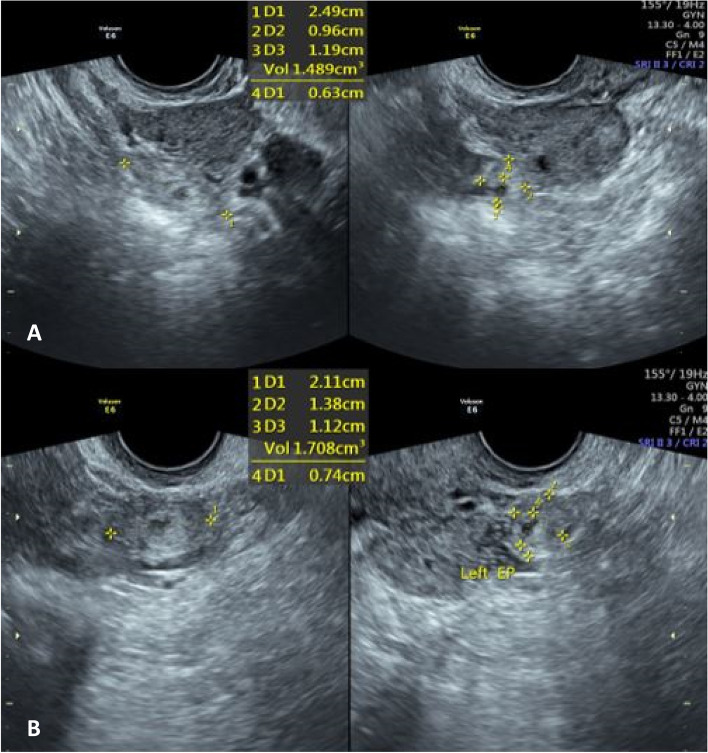

Fig. 1.

A heterogeneous tubular mass measuring 24*9*11 mm and 1.4 cc is seen adjacent to the right ovary (A). Another similar mass measuring 21*13*11mm and 1.7 cc is seen near the left ovary (B), suspected of bilateral unruptured ectopic pregnancies